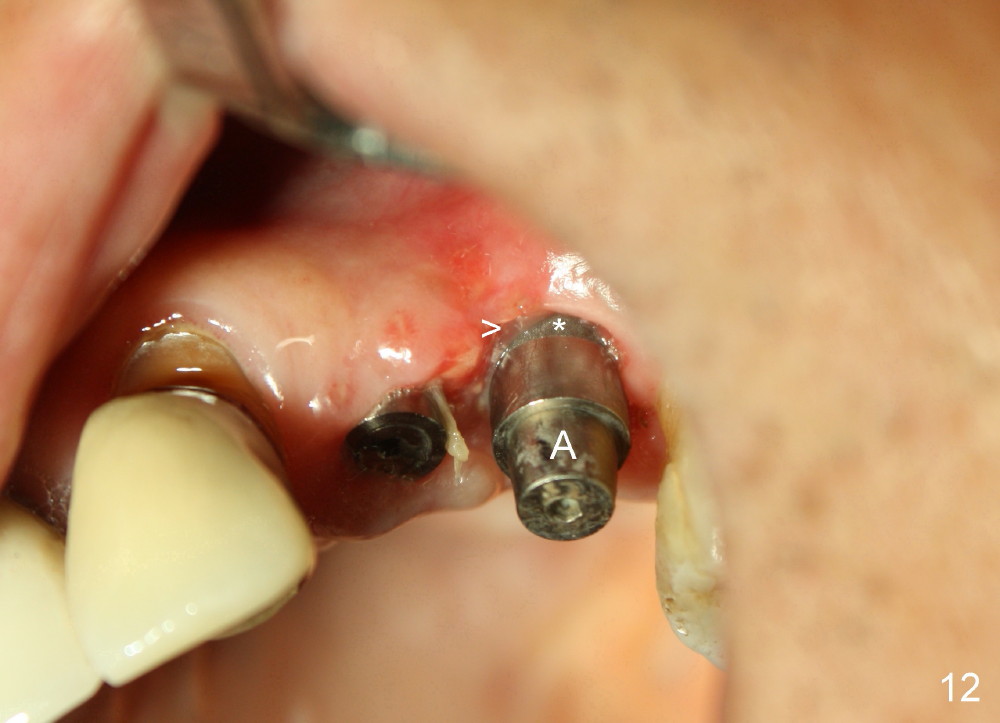

The perio dressing dislodges 18 days postop (Fig.12). By that time, the extraction wound has healed. The exposed rough surface of the implant (*) is most likely to be covered by fresh and healthy granulation tissue (>) underneath the gingiva. Subsequently the abutment (A) is removed, since it has finished its temporary function.